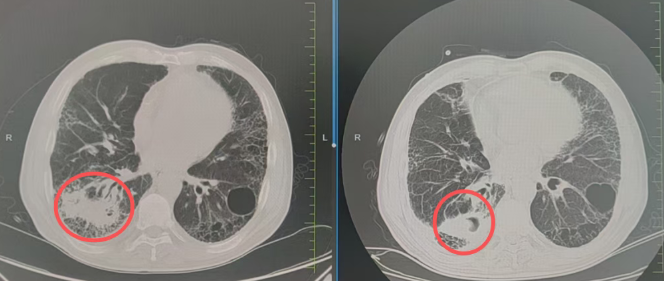

近日,长春国文医院肿瘤特需病区在张春禹主任的带领下,凭借医院已配备的瓦里安及医科达直线加速器等国际前沿放疗设备与技术体系,成功救治一名辗转多家医院、咯血久治不愈的肺癌患者。以亚毫米级精准定位与智能剂量优化,高效破坏肿瘤血管、实现即刻止血,同时最大程度保护周围正常组织,为肺癌急症患者实现了“止血”与“安全”的双重保障。

患者确诊肺癌3年,几个月前咯血症状反复加重,为求救治,患者及家属先后奔波于多家知名医院,接受了多种治疗方案,却始终无法有效控制出血,病情持续恶化让全家陷入绝望。抱着“最后一丝希望”,患者慕名转入长春国文医院肿瘤特需病区。

接诊后,张主任带领病区医疗护理团队立即启动紧急救治流程,通过多学科联合会诊(MDT),结合患者病史、影像资料与身体状态,精准定位出血病灶,全面评估治疗风险。针对患者病情,团队果断依托医院核心优势——国际前沿的放疗设备与技术体系,制定个体化精准放疗方案,直击病灶根源。

我院肿瘤特需病区配备瓦里安及医科达直线加速器等尖端设备,构建起“全维度精准放疗”技术壁垒:凭借亚毫米级精准定位与智能剂量优化,可实现射线“零误差”聚焦病灶,在高效破坏肿瘤血管、彻底止血的同时,最大程度保护周围正常肺组织、气管及心脏等重要器官;因患者既往双肺间质性肺炎、肺大疱等问题,从定位到治疗全程实时监控,确保每一次射线都精准覆盖肿瘤,同时将副作用降至最低。

经过规范、系统的精准放疗,困扰患者许久的咯血症状完全消失,睡眠、饮食逐步恢复正常,精神状态好转。复查结果显示,肿瘤病灶缩小,各项生命指标平稳。